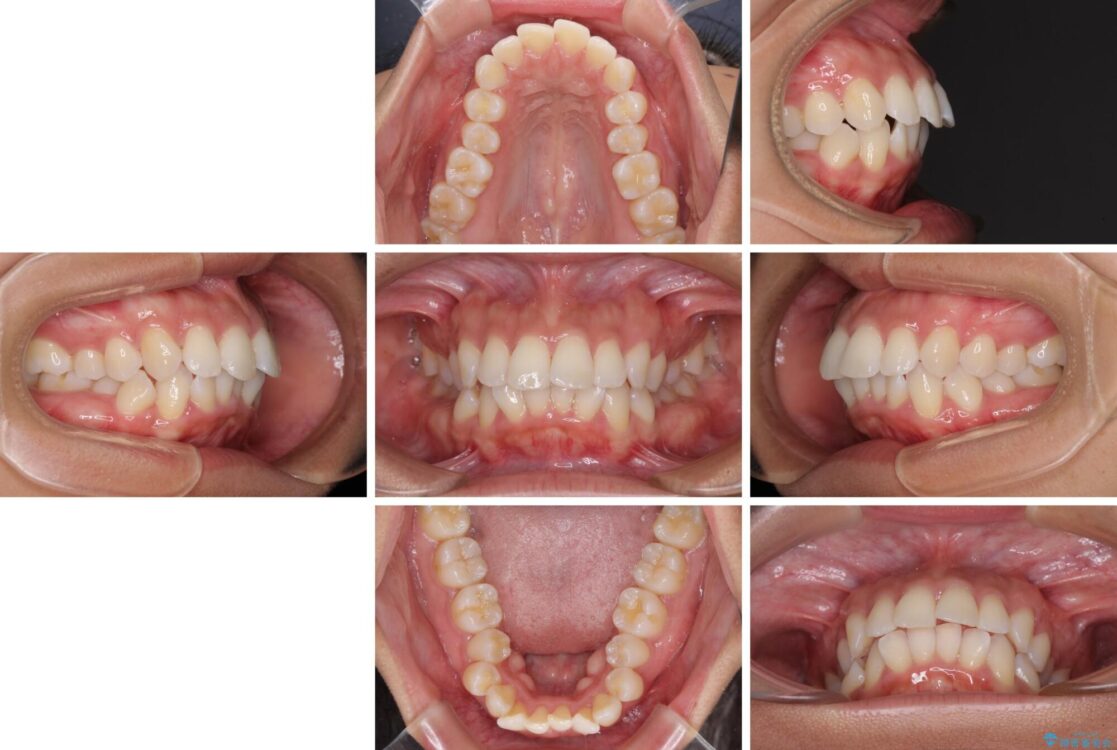

下唇が突き出るような口元の突出感が気になるとのことで来院された患者様です。

上下顎ともに前突した歯列であったので、上下ともに左右の第1小臼歯4本を抜歯し、ワイヤー装置にて矯正治療を行うこととしました。

治療前

• 抜歯矯正で唇を閉じやすく 目立たないワイヤー装置 治療前画像